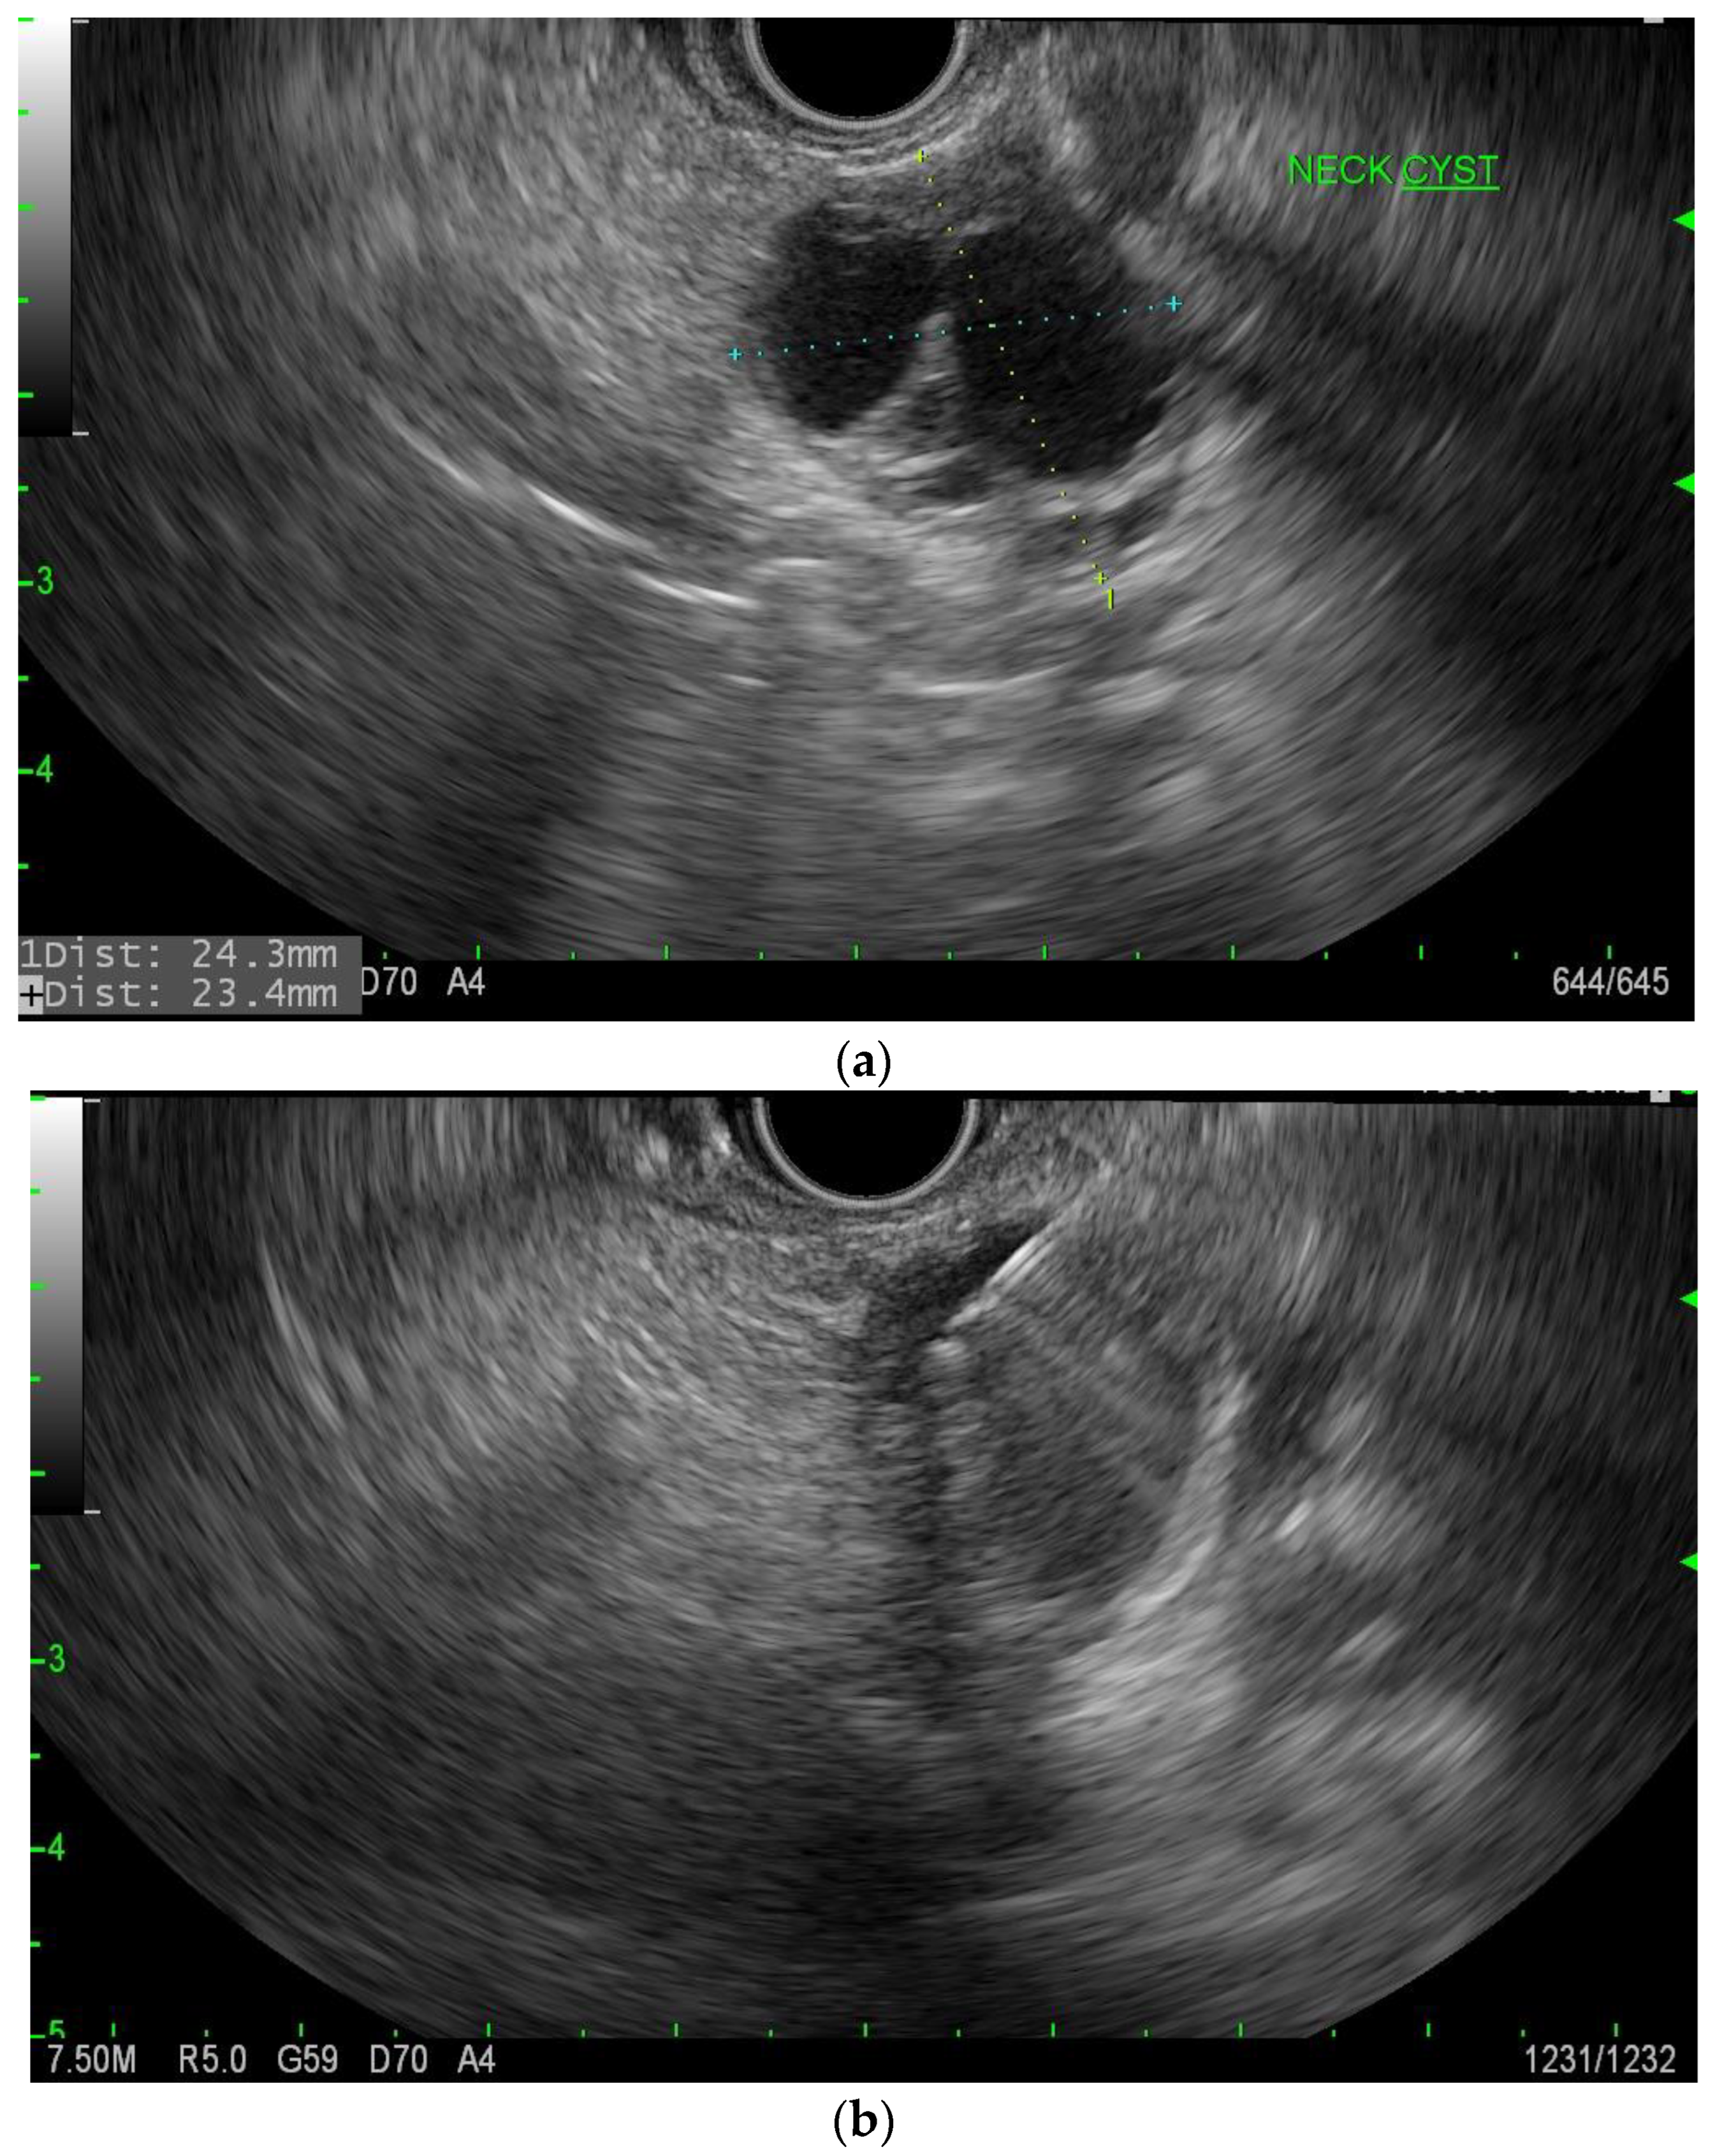

IPMNs can be divided into main duct intraductal papillary mucinous neoplasm and branch duct intraductal papillary mucinous neoplasms, with dilation of the main pancreatic duct helping to distinguish between the two. They usually present in the fifth to seventh decade of life and have an equal distribution between males and females [15]. Intraductal neoplasms are typically associated with a dilated main pancreatic duct (Figure 2a,b), whereas the branch duct IPMNs are associated with a dilated pancreatic duct branch or branches (Figure 3). A mixed IPMN is defined as a cystic lesion with ductal communication and main pancreatic duct dilation greater than or equal to 5 mm (Figure 4). Diabetes mellitus (DM) and a family history of pancreatic adenocarcinoma are known risk factors for IPMN, with odds ratios of 1.79 (CI 95%: 1.08–2.98) and 2.94 (CI 95%: 1.17–7.39), respectively [16]. Cytology can show columnar cells with variable atypia and can stain positive for mucin. CEA is usually greater than 200 ng/mL in approximately 75% of lesions, similar to mucinous neoplasms. Main duct IPMNs have a 36–100% risk of malignant potential, compared to a lower risk of 11–30% malignant potential of side branch IPMNs [17].

Figure 3.

MRI image of side branch IPMN.

Figure 4.

MRI image of mixed IPMN.